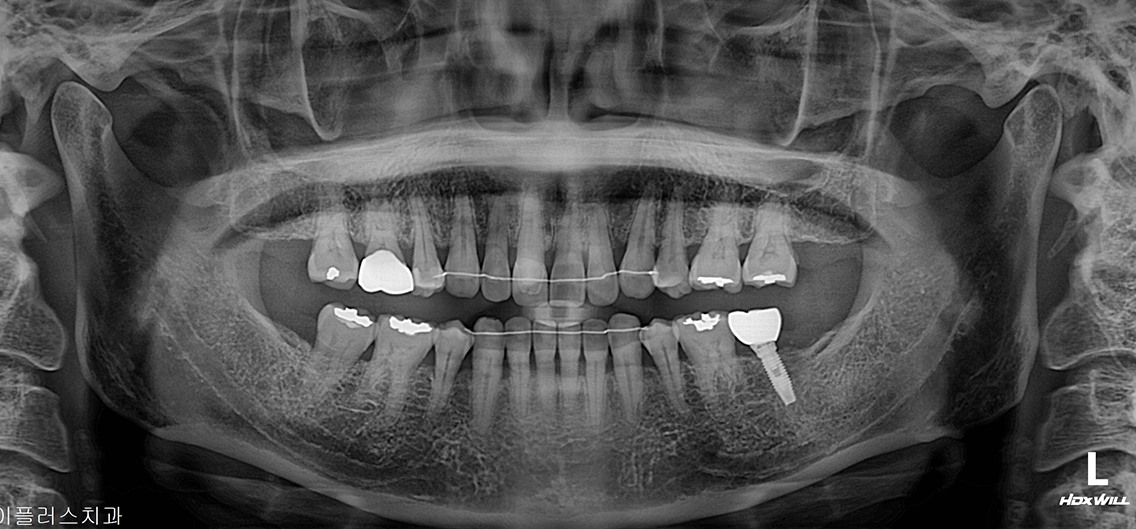

정밀 CT 촬영과 구강 검사를 통해 잇몸·뼈 상태를 확인하고, 개인에게 가장 적합한 임플란트 치료 계획을 세웁니다.

A+ 임플란트의 다양한 케이스를 확인해보세요.